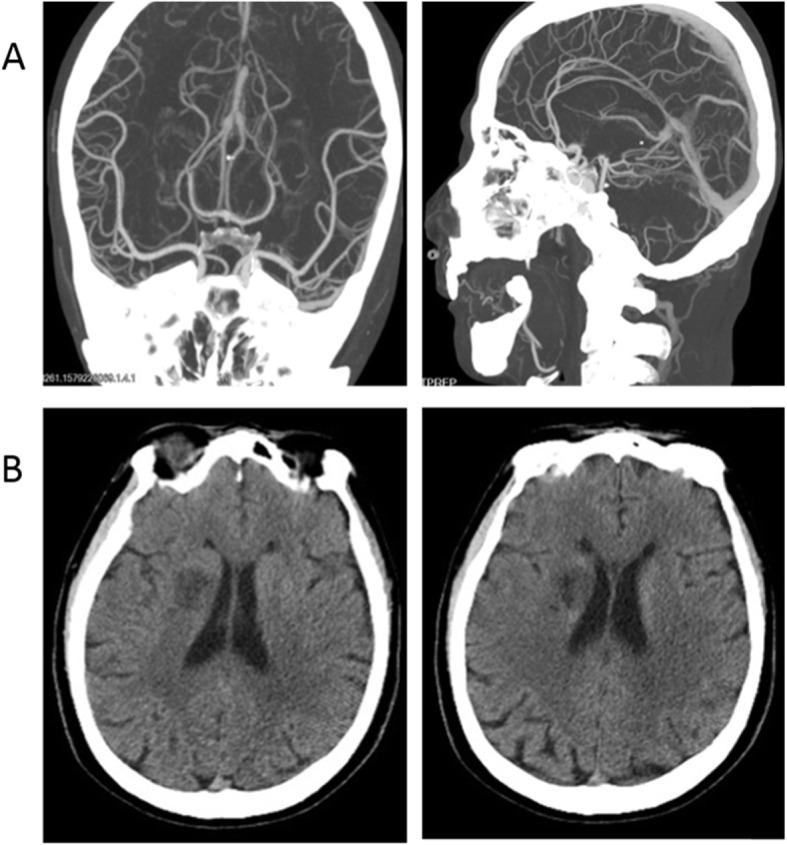

We here report two cases of coronavirus-infected pneumonia with acute ischemic stroke in middle-aged patients. In both COVID-19 cases, neurological physical examinations showed normal results before infection. Lymphocytopenia, accompanied by elevated cytokines and D-dimers, were found from serum clinical laboratory examination at admission. Dysarthria and limb muscle weakness are initial manifestations, occurring one week after infect-causative pathogen, SARS-CoV-2. The head CT and head/neck arterial CTA showed small-vessel occlusion. The patients were diagnosed with coronavirus diseases with secondary acute ischemic stroke. They were treated with tirofiban and followed up with daily aspirin and atorvastatin.

These cases suggested that secondary ischemic stroke, mainly manifested as small-vessel occlusion, should be considered for COVID-19 patients and diagnosed and treated promptly.